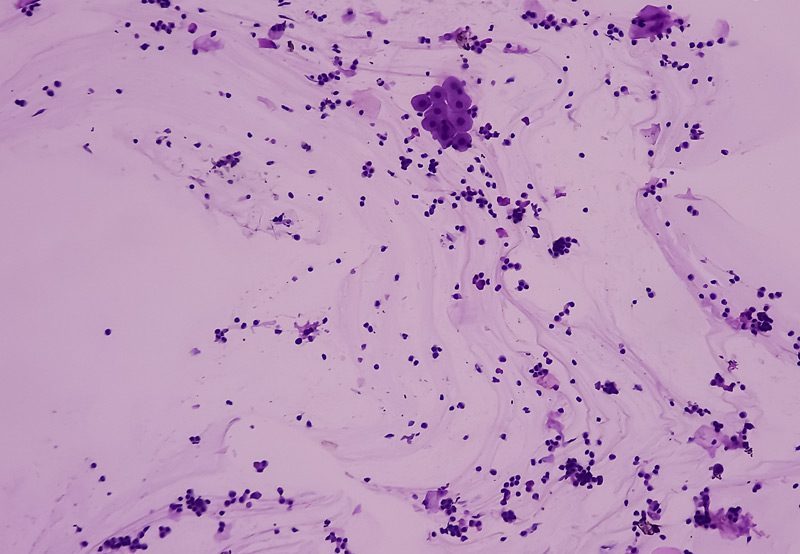

- Urine cytology: To detect abnormal cells in the urine